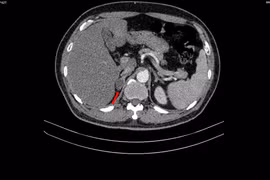

Tại Bệnh viện Bệnh Nhiệt đới Trung ương, kết quả cận lâm sàng cho thấy hệ miễn dịch của bệnh nhân bị suy kiệt nghiêm trọng. Chỉ số viêm CRP tăng vọt tới 348 mg/l (cao gấp hơn 70 lần mức bình thường), trong khi Procalcitonin đạt ngưỡng 100 ng/ml và bạch cầu giảm sâu xuống còn 1,94 G/L.

Trên lâm sàng, các nốt thủy đậu phủ khắp cơ thể, có nhiều nốt đã hóa đục kèm theo biểu hiện sốc nhiễm khuẩn và nhiễm trùng ổ bụng nặng. Siêu âm ghi nhận nhiều dịch tự do trong ổ bụng, có ổ dịch kích thước lên tới 36mm.